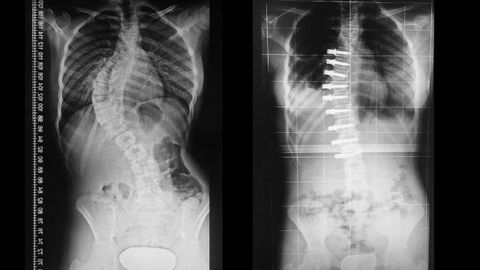

La paciente presentaba una desviación de columna de un 65 %. Después de la operación, la curva se redujo a 12 grados y, con el tiempo, se quedará en 7. Al día siguiente ya podía sentarse y una semana después hacía vida normal. Fue posible gracias a una técnica pionera practicada por primera vez en España por el Hospital Universitario Dexeus que permite corregir la escoliosis idiopática adolescente, una patología que sufren uno de cada diez menores, manteniendo la movilidad de la columna mientras se va corrigiendo el grado de la curva.

El procedimiento habitual se basa en colocar tornillos en las vértebras afectadas y dos barras que fijan la columna en la posición correcta, pero imposibilitando el movimiento de la misma y limitando la capacidad en la vida diaria de los pacientes. Por contra, la nueva técnica se realiza por vía torácica y se colocan la mitad de los tornillos. Además, estos se unen mediante una cuerda, de manera que no pierden flexibilidad.